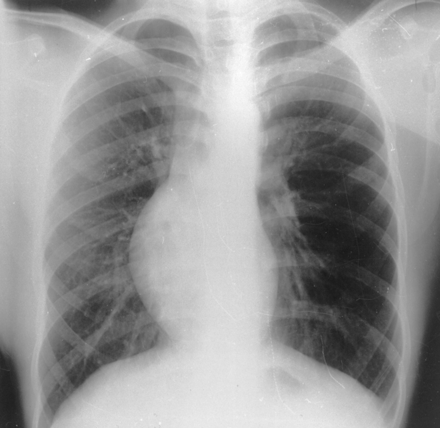

Поланда синдром (Poland syndrome)

Синдром Поланда (СП) представляет собой комплекс пороков, включающий отсутствие большой и малой грудной мышц, синдактилию, брахидактилию, ателию (отсутствие соска молочной железы) и/или амастию (отсутствие самой молочной железы), деформацию или отсутствие нескольких ребер, отсутствие волос в подмышечной впадине и снижение толщины подкожно-жирового слоя. Отдельные компоненты этого синдрома впервые были описаны Lallemand LM (1826) и Frorier R (1839). Однако назван он по имени английского студента-медика Alfred Poland, который в 1841 году опубликовал частичное описание данной деформации. Полную характеристику синдрома в литературе впервые опубликовал Thompson J в 1895 году.